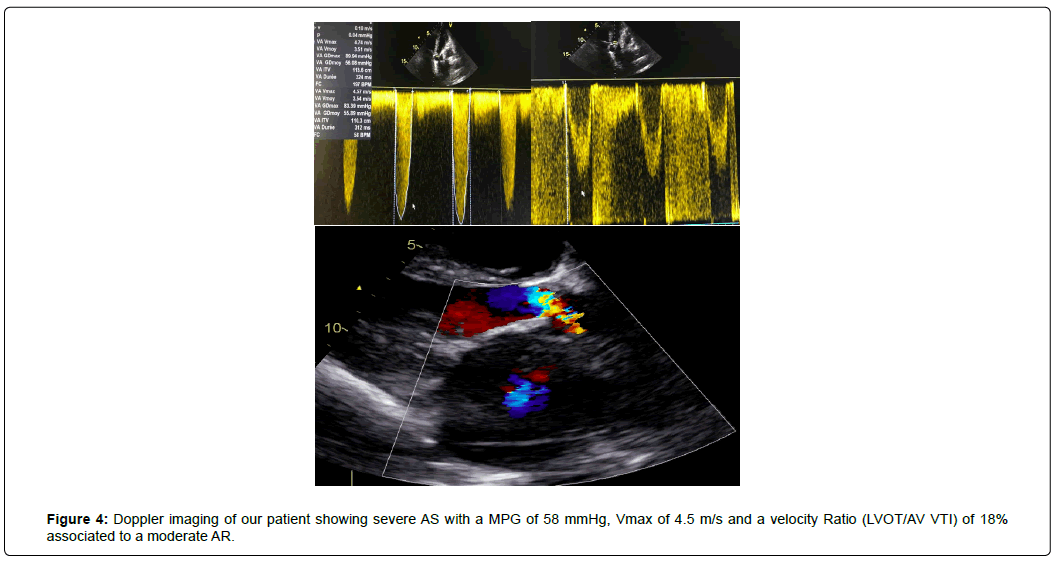

In addition to this, a severe Aortic Stenosis (AS) with a MPG of 58 mmHg, peak aortic valve velocity (Vmax) of 4.5 m/s and a velocity Ratio of 18% associated to a moderate Aortic Regurgitation (AR), were assessed (Figure 4).

We initiated medical therapy in our patient with low dose furosemide (40 mg/Day), Acenocoumarol 4mg and Digoxin 0.25 mg/Day for her AF. The case was then discussed by the heart-team who decided to try a transcatheter approach given the patient’s high surgical risk, by dilating the aortic valve first, then the mitral and finally the tricuspid valves, in order to avoid sudden increase in cardiac output that may worsen the transaortic valve gradient in case the mitral valve was dilated first.